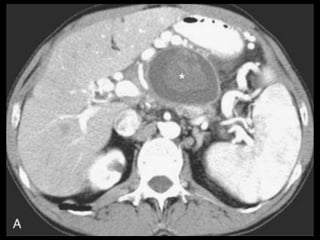

Pseudocistos

Coleções encapsuladas e uniloculadas de líquido

pancreático e material necrosado e proteináceo;

São necessárias 4 semanas ou mais para que um

pseudocisto evolua de uma coleção líquida aguda;

Mais comumente peripancreáticos, mas podem ser

observados no mediastino e na pelve;

Importância do contraste oral positivo;

Metade dos pseudocistos regride

Pseudocistos-TC

Coleção líquida redonda ou oval, com uma parede

fina ou espessa, que apresenta intensificação pelo

contraste;

RM: lesão uniloculada bem definida, hipointensa

em T1 e hiperintensa em T2;

Bolhas de gás: infecção, fístula ou à cistostomia

interna;

Hemorragia aguda dentro do cisto: hiperdensa

Estenose ou oclusão venosa, com formação de

varizes ou pseudoaneurismas.